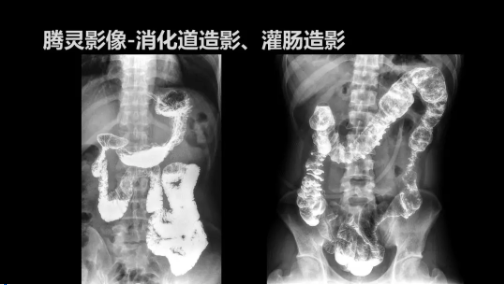

“騰靈”是安健科技的第四代動(dòng)態(tài)DR產(chǎn)品,可實(shí)現(xiàn)全科室應(yīng)用。如各類常規(guī)的X線檢查、消化道檢查、骨科檢查、婦科、兒科檢查等。此外,安健科技為“騰靈”在真正意義上實(shí)現(xiàn)多科室、多功能診斷進(jìn)行了多項(xiàng)針對(duì)性設(shè)計(jì)。